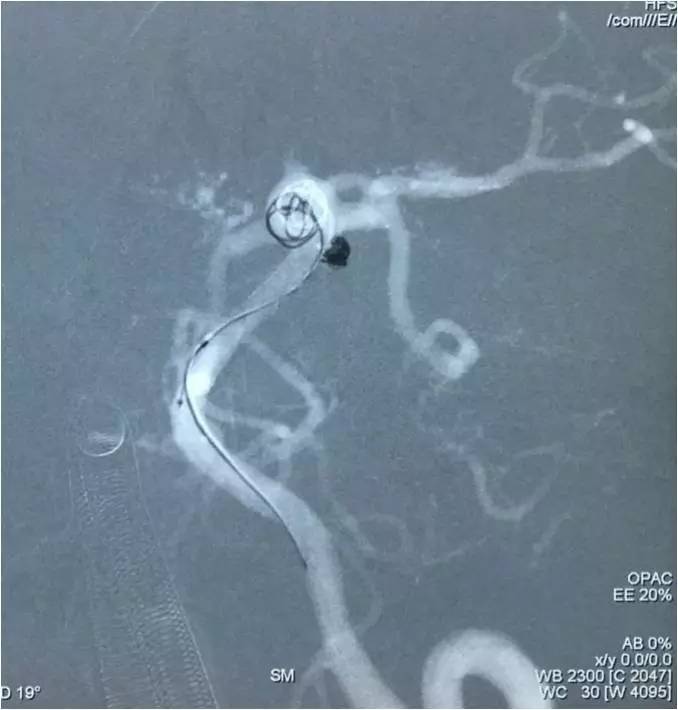

▼左椎动脉工作位造影,可以清晰暴露基底动脉顶端动脉瘤及其子瘤、左小脑上动脉瘤。

▼Headway17导入左PCA P2段,用于备放LVIS JR支架;Echelon10微导管送入基底动脉顶端动脉瘤瘤腔内,送入第一枚弹簧圈QC-4-12-3D,弹簧圈送出约一半长度,在瘤腔内盘旋,一定程度上能有助于防止后续释放的支架陷入瘤腔。

▼经预置的Headway17送入LVIS JR 3.5*23支架,跨瘤颈释放入左PCA-基底动脉内,蒙片显示支架张开良好。